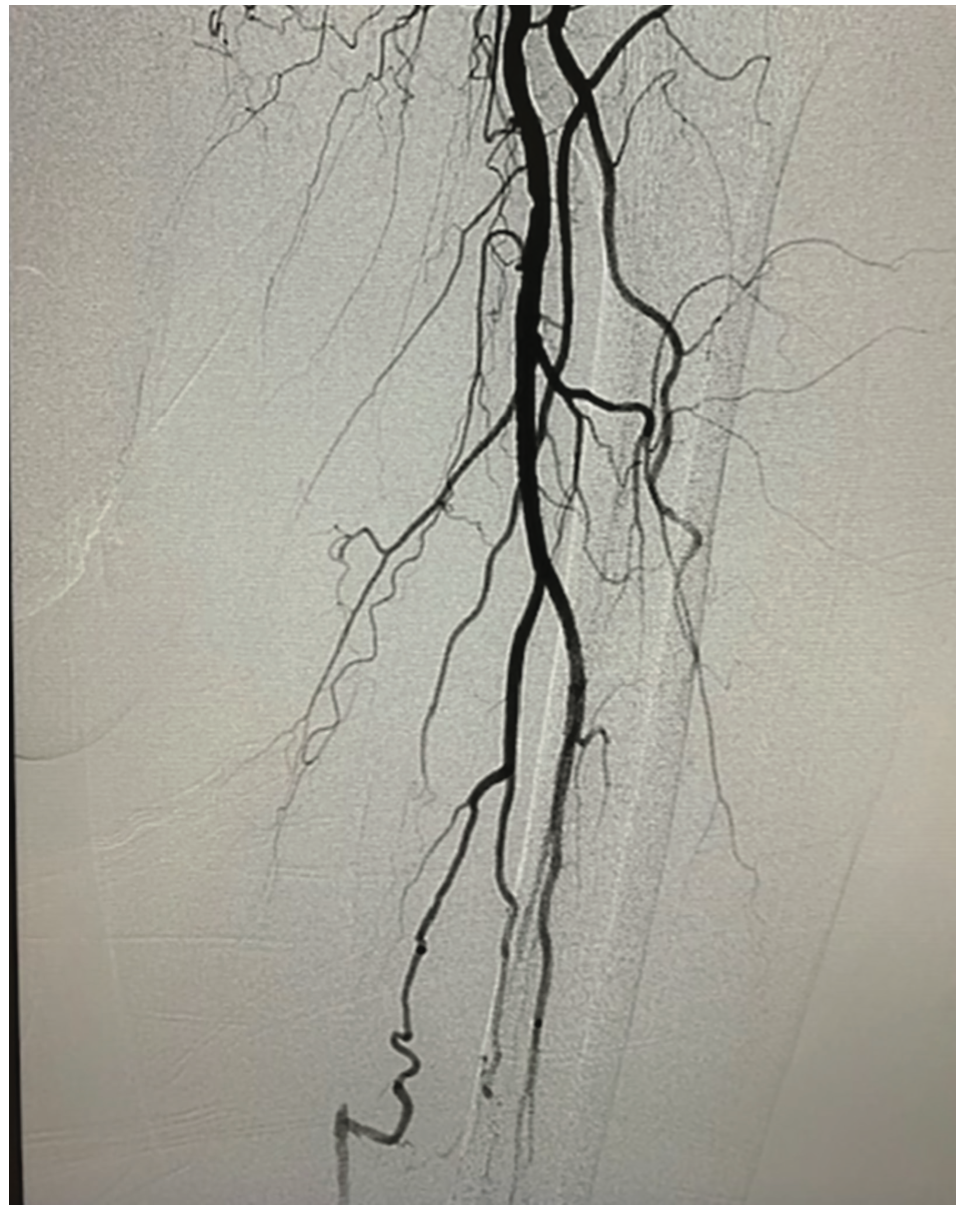

The right groin was accessed under ultrasound guidance. With a 5 French sheath, we crossed with a internal mammary artery (IMA) catheter and performed selective left lower extremity angiography. The SFA was occluded, although there appeared to be a possible beak (Figure 1). The vessels reconstituted distally just prior to adductors canal via profunda collaterals. Distally, there was visualization of the anterior tibial and peroneal arteries which appeared patent, with the posterior tibial filling last.